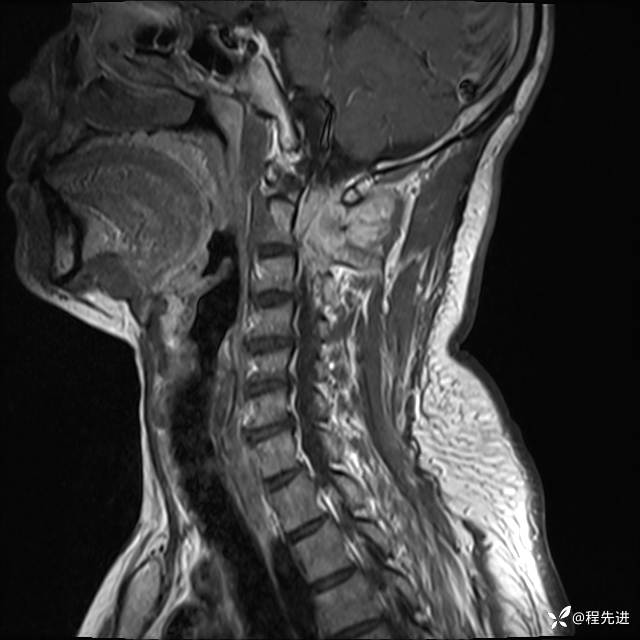

MRI平扫+增强:

T2:

T1:

T1增强: